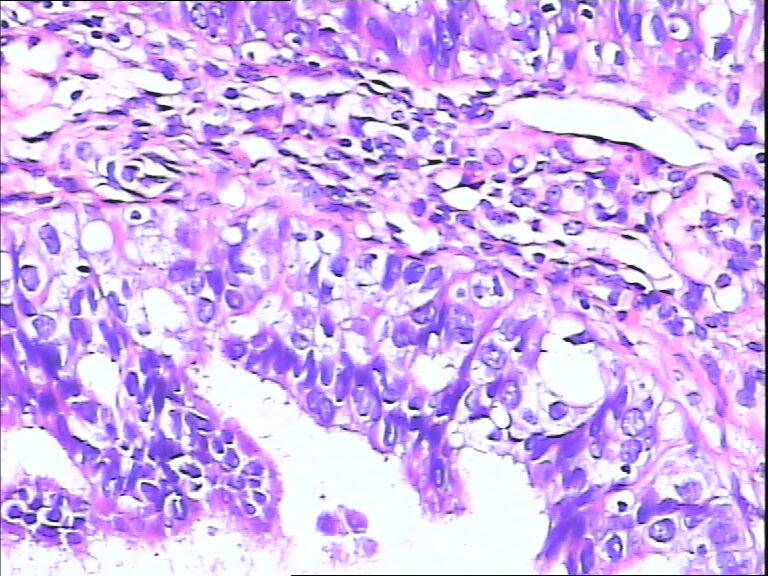

女,43y

左输卵管积液

输卵管长4.5cm;直径:0.8cm

• 请教:输卵管!图1

图1

输卵管增生性上皮病变。

慢性炎伴上皮增生

良性,炎症改变

考虑炎症